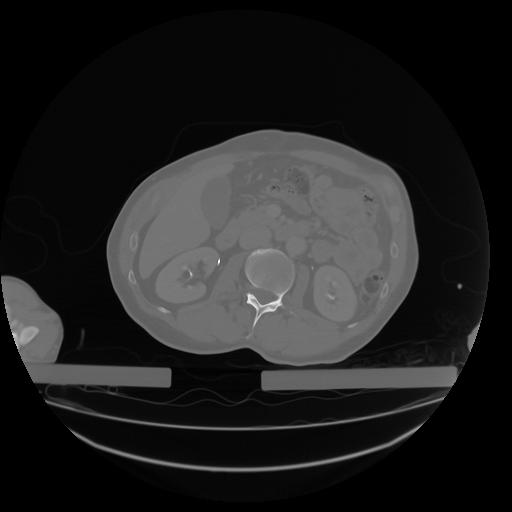

27 CUERPO,CE,Axial,3.0,CUERPO,,